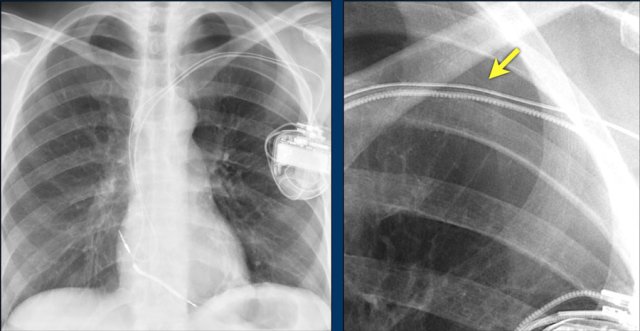

Here another patient with the Twiddler's syndrome.

Notice curling of the lead near the pacemaker and at the tip in the right ventricle (arrows).

Here another patient with Twiddler.

There was malfunction of the pacemaker.

A new pacemaker was inserted on the right side.